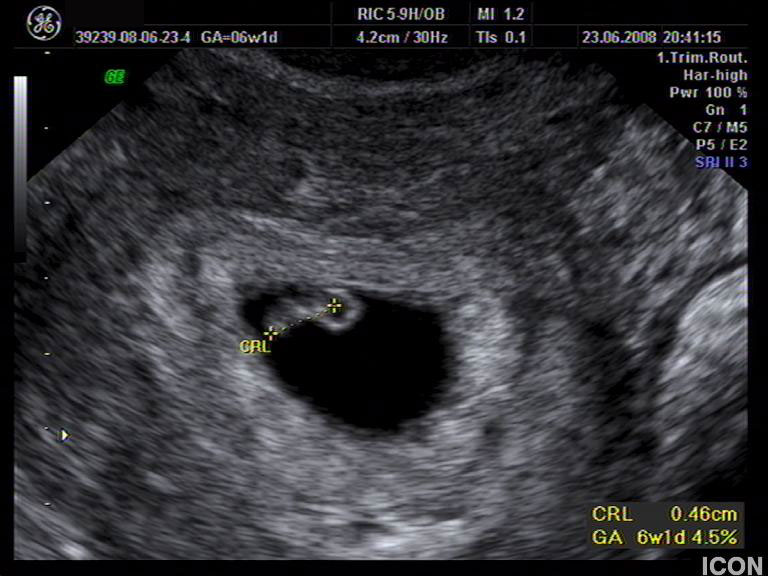

Αυχενική διαφάνεια

Η αυχενική διαφάνεια (ΑΔ) είναι η συλλογή υγρού στον τράχηλο του εμβρύου και συγκεκριμένα ανάμεσα στο δέρμα και στους ιστούς που καλύπτουν τη σπονδυλική στήλη.